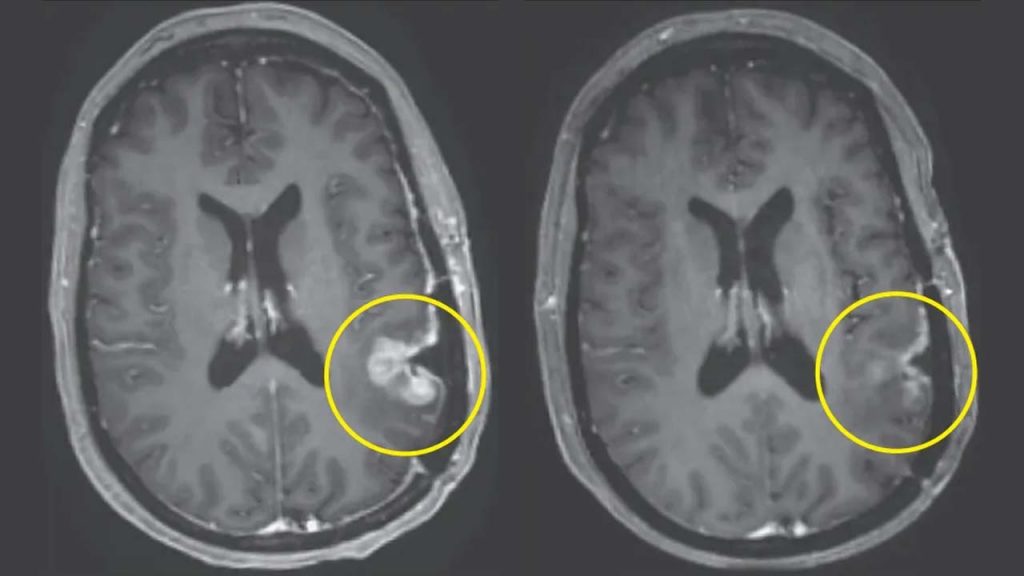

మాస్ జనరల్ క్యాన్సర్ సెంటర్లో జరిగిన క్లినికల్ ట్రయల్లో, గ్లియోబ్లాస్టోమాతో బాధపడుతున్న ముగ్గురు రోగుల ట్యూమర్లు ఒకే డోసు ప్రయోగాత్మక సెల్ థెరపీ తీసుకున్న తర్వాత గణనీయంగా కుదించుకుపోయాయి. వాటిలో కొన్ని ట్యూమర్లు కేవలం కొన్ని రోజుల్లోనే తగ్గాయి. ఈ చికిత్స, CAR-T థెరపీలోని ఒక వెర్షన్. ఇందులో రోగి స్వంత రోగనిరోధక కణాలను ఉపయోగిస్తుంది. వీటిని క్యాన్సర్ను మరింత సమర్థవంతంగా గుర్తించి దాడి చేయడానికి మళ్లీ ప్రోగ్రామ్ చేస్తారు. ఈ క్లినికల్ ట్రయల్స్ లో ఒక రోగి ట్యూమర్ దాదాపు పూర్తిగా మాయం అయ్యింది. మరొకరి ట్యూమర్ 60% కంటే ఎక్కువగా కుదించి, ఆ స్థితిలోనే ఆరు నెలలకు పైగా కొనసాగింది. కొత్త బ్రెయిన్ క్యాన్సర్ చికిత్స ఒకే డోసుతో ప్రాణాంతకమైన మెదడు ట్యూమర్ను కేవలం కొన్ని రోజులలోనే కుదించింది.

ట్యూమర్లు చివరికి తిరిగి పెరిగినా, ఈ వేగవంతమైన ప్రతిస్పందన తక్కువ చికిత్సా అవకాశాలు ఉన్న, ప్రస్తుత థెరపీలకు ప్రతిఘటించే ఈ క్యాన్సర్కు కొత్త ఆశను కలిగిస్తోంది.